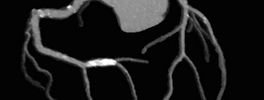

• Calcium scoring and coronary angiography

CT Heart